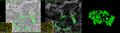

Cell segmentation on 3D SIM data. The segmentation mask is overlayed on 4D LSM data for spectral analysis.

Individual granules (Lipofuscin (bright) and Melano-lipofuscin (dark)) in a zoomed view of LSM and SIM.